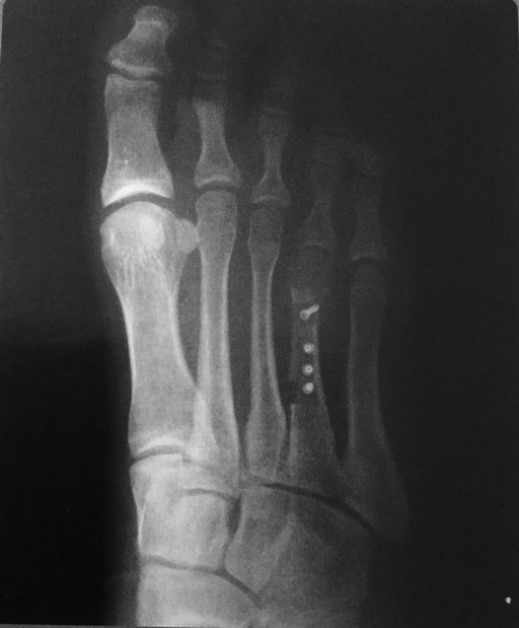

En cuanto a los procedimientos quirúrgicos, los hay graduales donde podemos conseguir más de 1,5 cm, y procedimientos de alargamiento en una sola etapa, donde podemos conseguir hasta un máximo de 1,5cm.

Para los alargamientos graduales están los mini fijadores externos, y para los alargamientos en una sola etapa se encuentran los injertos óseos, placas y sustitutos óseos.

Radiografía de Postoperatorio alargamiento con injerto óseo y mini tornillos canulados.